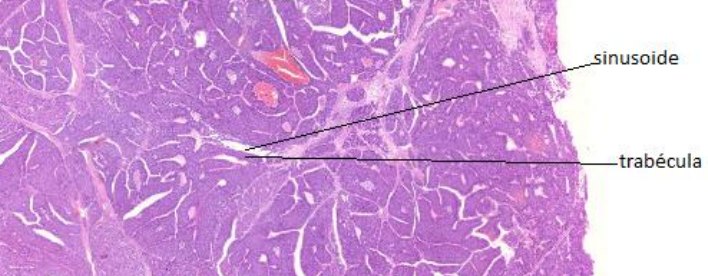

Carcinoma hepatocelular bem diferenciado (A475)

Macrotrabéculas

Necrose

Atipia